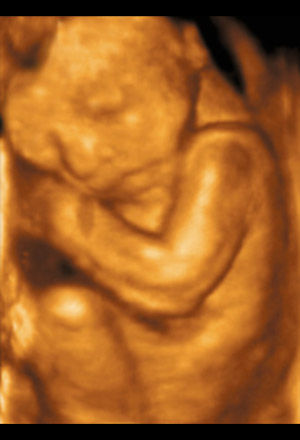

By the sixth month, the baby weighs in at about 0.6 kilogram (1.4 pounds) and 30 cm (11.8 inches) in total length. It can hear your voice, heartbeat and breathing, responds to sounds by moving or increasing its pulse, so now's a great time to start reading and talking to your baby. You may notice jerking motions if it hiccups. The baby is also depositing brown fat, which will help it regulate body temperature at birth.